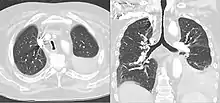

CT scan of a saber-sheath trachea in a patient with COPD

A saber-sheath trachea also known as scabbard trachea is a trachea that has an abnormal shape. The posterior area of the trachea increases in diameter while the lateral measurement decreases.

It can occur in chronic obstructive pulmonary disease or prolonged bilateral compression on it as in goitre.